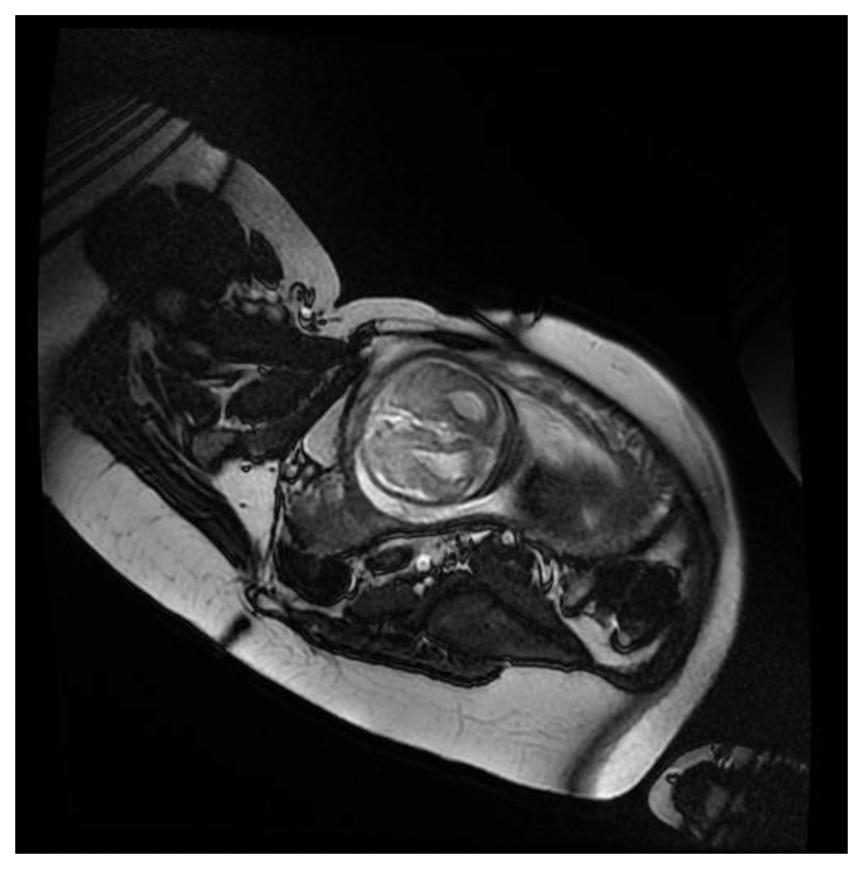

Figure 7 show a fECG gated fetal image from one of the volunteers at the end of the normal CNS exam using a gradient echo cardiac gated imaging sequence (Right Ventricle Long Axis (RVLA) sequence) but using the geometry as planned for the CNS examination.